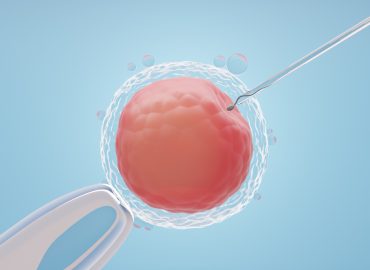

Üreme Sağlığında İleri Teknolojiler: Tüp Bebek ve IVF Tedavileri

Modern tıbbın sunduğu ileri teknolojiler, üreme sağlığında devrim niteliğinde gelişmeler kaydetmemizi sağlamıştır. Tüp bebek ve IVF (In Vitro Fertilizasyon) tedavileri, bu alanda en dikkat çekici ve umut verici yöntemler arasında…